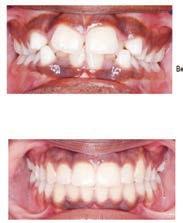

๊ฑด๊ฐํ ๋ฏธ์, ํดํผ์ค๋ง์ผ ์น๊ณผ์์

์ต์ ์ฅ๋น์ ์น์ ํ ์ง๋ฃ, ์ํ๋ํธ๊น์ง ๋ฏฟ๊ณ ๋งก๊ธฐ์ธ์!

ํนํ ํดํผ์ค๋ง์ผ ์น๊ณผ๋ ์ํ๋ํธ ์น๋ฃ

์ ๊ฐํ ์์ ๊ฐ์ ๊ฐ์ง๊ณ ์๋๋ฐ, ์์์

์น์ ๋ ์ฌ์ฉํ๋ ํ, ์ฆ ์น์์ ํฑ ๊ทผ์ก

์ ์ฌ์ฉํ์ฌ ์์์ ์๊ฒ ๋ถ์๋ ๋ฅ๋ ฅ๊ณผ

์ฌ๋ฏธ์ฑ์ ๋์์ ๋ง์กฑ์ํค๋ ์ํ๋ํธ๋

์์ฐ ์น์์ ๊ฐ์ฅ ๊ฐ๊น์ด ๋์ฒด ์น๋ฃ๋ก, ํ

๋์ ๋นํด ๋ ๋จ๋จํ๊ณ ์ค๋ ์ฌ์ฉํ ์ ์

์ธ์ ์น์๋ฅผ ๊น์ ํ์๊ฐ ์์ด ๊ตฌ๊ฐ ๊ฑด๊ฐ์ ์ ์งํ๋ ๋ฐ๋ ๋์์ด ๋๋ค. ํดํผ์ค๋ง์ผ ์น๊ณผ๋ ๋ณต์กํ ๊ตฌ๊ฐ์ธ๊ณผ ์์ ๊ณผ ์ง๋จ์ ์ํด ์น๊ณผ์ ์ฉ 3D CT ์ค์บ๋๋ฅผ ๊ฐ์ถ๊ณ ์์ผ๋ฉฐ, ์ด๋ฅผ ํตํด ์ ํํ๊ณ ์์ ํ ์ํ๋

ํธ ์์ ์ด ๊ฐ๋ฅํ๋ค. ํฑ๋ผ ์ํ, ์ ๊ฒฝ ์์น, ๋ผ์ ๋ฐ๋๊น์ง ์ ๋ฐํ๊ฒ ๋ถ

์ํ์ฌ ํ์ ๊ฐ๊ฐ์ธ์๊ฒ ์ต์ ํ๋ ์น๋ฃ ๊ณํ์ ์๋ฆฝํด๋๋ฆฐ๋ค.

๋ฟ๋ง ์๋๋ผ, ์ฌ๋ฏธ๋ณด์ฒ ๊ณผ ๋ฏธ์ฉ์น๋ฃ, ์ผ๋ฐ์น๊ณผ, ์์์น๊ณผ, ๊ตฌ๊ฐ์ธ๊ณผ, ์ ๊ฒฝ

์น๊ณผ ๋ฑ ๋ค์ํ ๋ถ์ผ์ ์ ๋ฌธ ์๋ฃ์ง์ด ํจ๊ปํด ํ ํ ์น๊ณผ ์ง๋ฃ๋ฅผ ์์คํฑ ์ผ๋ก ์ ๊ณตํ๊ณ ์๋ค.

ํดํผ์ค๋ง์ผ ์น๊ณผ์์๋ ์ ํธ๋(Aetna), ์ค์ฌ(Anthem), ํด๋ ๋ฒ์ผ์ด (Clever Care), ์์คํฐ๋ฐ(Astiva), ํด๋จธ๋(Humana), ๋ฆฌ๋ฒํฐ(Liberty), ์ ๋ ์ดํฐ๋ํฌ์ค์ผ์ด(United Healthcare) ๋ฑ. ๋ค์ํ ๋ณดํ์ ์ทจ๊ธํ๊ณ ์๊ณ , ๋ฉ๋์นผ/๋ฉ๋์ผ์ด PPO ๋ณดํ ํ์ํ๋ค.

์ข์ ์ฌ๋ฃ์ ๊ณ ํ์ง ์ง๋ฃ, ์ต์ ๊ธฐ์ , ๊ทธ๋ฆฌ๊ณ ํ์๋ฅผ ์๊ฐํ๋ ์ง์ฌ์ด ์๋ ํดํผ์ค๋ง์ผ ์น๊ณผ์์ ์จ ๊ฐ์กฑ์ ๊ฑด๊ฐํ ๋ฏธ์๋ฅผ ๋์ฐพ์๋ณด์.

๋ฌธ์ ๋ฐ ์์ฝ: 818-775-1200